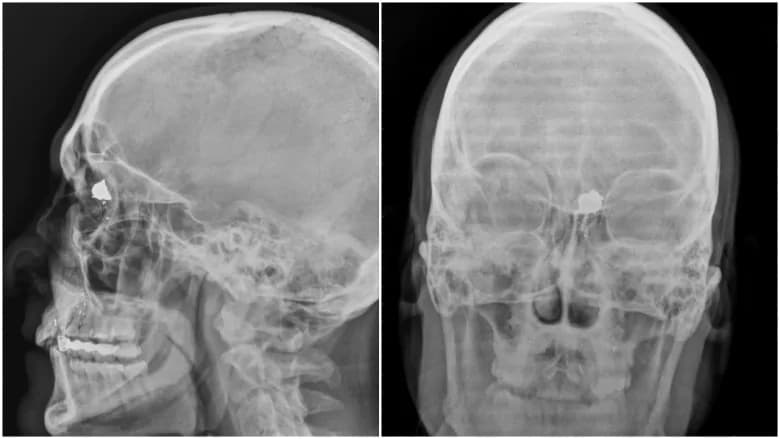

Um dia em seu rancho, ele pegou uma arma e colocou uma bala na cabeça. Ele sobreviveu.